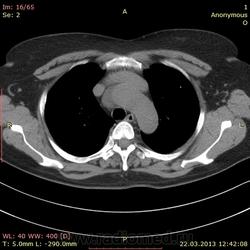

Пациентка 52 года. Поступила с жалобами на редкий сухой кашель, общую слабость, потливость, ощущение "лопания" в трахее, эпизодическое удушье. В ноябре 2012 перенесла двустороннюю полисегментарную пневмонию. Сейчас с подозрением на повторную пневомнию прислали на кт. В легких ничего особенного, а вот аорта меня заинтересовала.

Помогите с диф диагнозом. Думаю на расслоение аневризмы, но плотность этой штуки всего до 10 HU. Контрастирование не делаем, болюса нет((.

Пациентка 52 года. Поступила с жалобами на редкий сухой кашель, общую слабость, потливость, ощущение "лопания" в трахее, эпизодическое удушье. В ноябре 2012 перенесла двустороннюю полисегментарную пневмонию. Сейчас с подозрением на повторную пневомнию прислали на кт. В легких ничего особенного, а вот аорта меня заинтересовала.

Помогите с диф диагнозом. Думаю на расслоение аневризмы, но плотность этой штуки всего до 10 HU. Контрастирвоание не делаем, болюса нет((.

Ну, оценка аорты без контрастирования - это очень круто, но я бы отметил вероятность тромбированной аневризмы.

Про контраст я сама все понимаю(((( написала пока просто аневризма, ибо на декабрьских снимках эта штука тоже есть, и врач тогда не акцентировал внимание. В понедельник, думаю эхо делать будут...

Сделали узи. Никакого намека на аневризму. Видимо киста такая.

без контраста по первому же кадру ясно, что это целомическая киста перикарда, классическое расположение и форма.